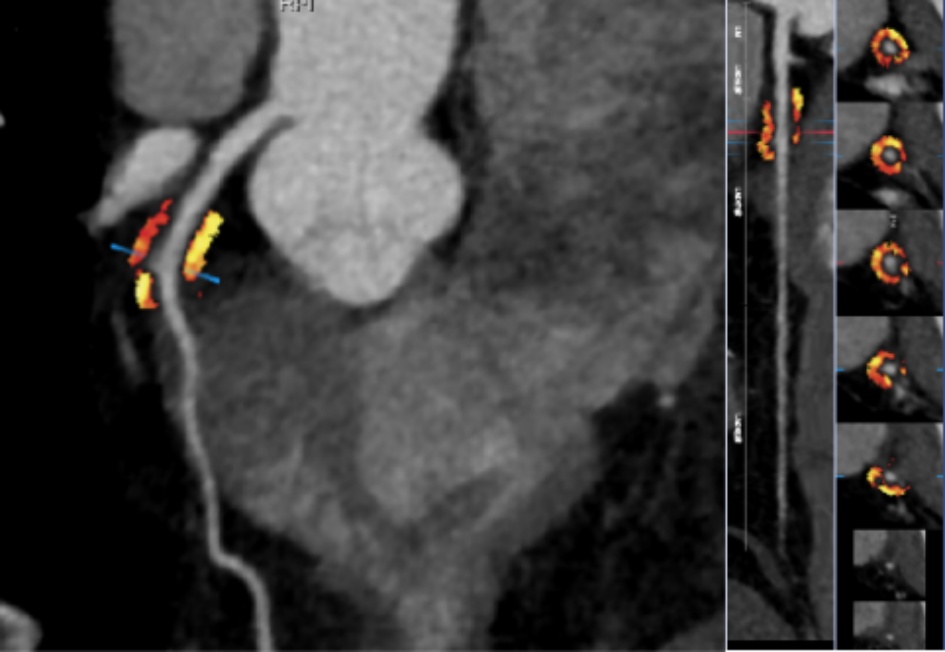

在本研究中,MB-MCA的长度与厚度测量均基于CCTA的收缩期图像进行,以准确反映心肌收缩时对血管的压迫特征。将所有冠状动脉图像数据导入后处理工作站,运用多平面重建(MPR)和曲面重建(CPR)等技术进行形态学参数提取。MB厚度的测量在垂直于MCA走行的MPR图像上进行,于收缩期选取心肌桥压迫最深的位置,测量从心肌外膜至动脉血管外侧壁的最大垂直距离,作为MB厚度[7]。MB-MCA长度的测量则在CPR图像上完成,于收缩期确定其入口(即开始被心肌覆盖的位置)与出口(心肌覆盖结束的位置),测量该段血管的长度即为MB-MCA长度(图2) [8]。为减少心肌桥导致的血管位移伪影对测量准确性的影响,本研究采用以下质量控制措施:① 所有图像均在收缩期重建,以最大程度减少运动伪影;② 对于图像中存在明显阶梯状伪影或血管边缘模糊者,予以排除;③ 所有测量均在MPR与CPR图像上反复确认,确保测量平面垂直于血管走行。所有测量工作由一名具有5年及一名具有8年CCTA诊断经验的心胸影像诊断医师独立完成。采用组内相关系数(ICC)进行观察者间一致性检验,结果显示两位观察者的测量结果一致性极佳(ICC > 0.90)。对于极少数存在分歧的测量结果,经协商后取得共识,并取其平均值作为最终结果,确保数据的客观性与准确性。此外,为确保两家医院数据的一致性,所有图像均由同一组专家采用统一的标准化流程进行后处理与测量,并进行了观察者间和观察者内的一致性检验(ICC > 0.90)。

Figure 2. Measurement methods of MB-MCA length and MB thickness

2. MB-MCA长度与MB厚度的测量方法

3.4. FAI测量

将患者收缩期原始图像上传至数坤网络科技人工智能平台进行分析,测量FAI值。FAI值以MCA-MB入口近端2 cm为纵向距离,以血管外壁直径为径向距离,测量范围为血管外壁到外圈周围组织。调整纳入计算的组织密度范围为−190~−30 HU,随后软件自动计算出斑块血管周围脂肪密度的平均值作为FAI (图3)。

Figure 3. Measurement method of FAI

3. FAI的测量方法